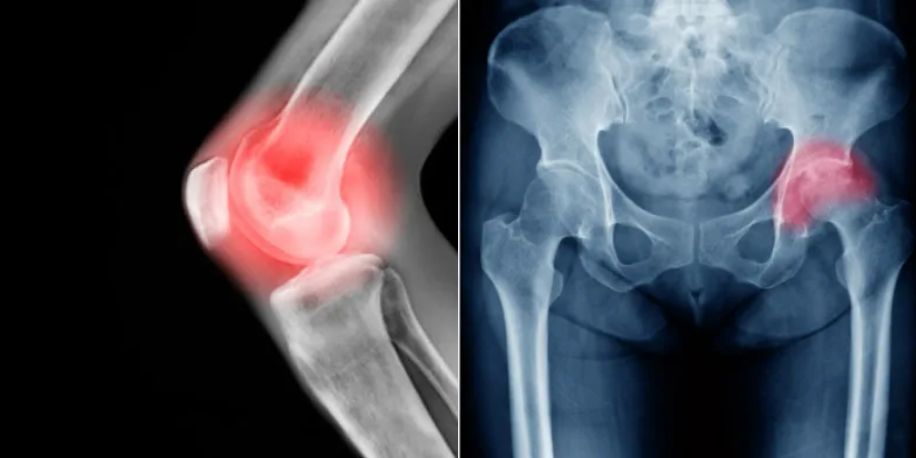

1. 骨关节炎治疗

骨关节炎是一种退行性关节疾病,传统治疗方法往往只能缓解症状,难以从根本上解决问题。PRP为骨关节炎的治疗带来了新的希望。将PRP注射到关节腔内,生长因子可以促进软骨细胞的再生和修复,抑制关节内的炎症反应,减轻疼痛,改善关节功能。长期使用,还能有效延缓骨关节炎的进展,让患者的关节重焕生机。

对于早期至中期的膝、髋、肩等关节骨关节炎,PRP注射能够显著缓解关节疼痛,改善关节功能,延缓疾病进展。多项临床研究显示,PRP治疗在缓解疼痛和改善功能方面优于传统的透明质酸注射。